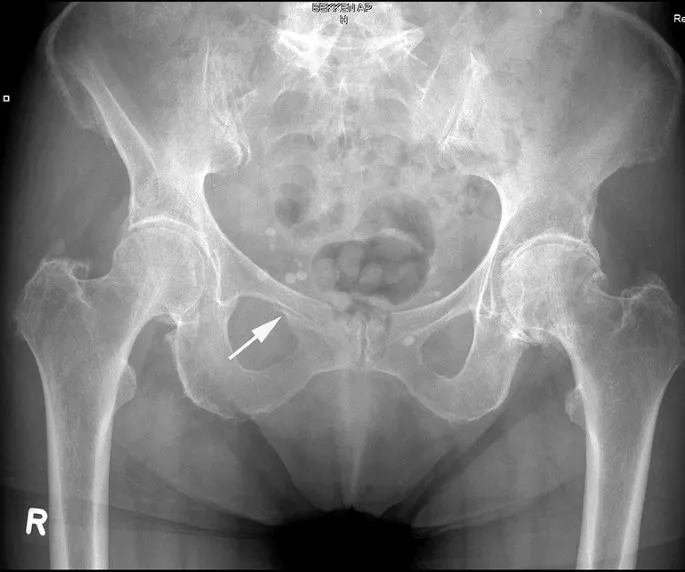

3.Beeldvorming: Bij vermoeden van een bekkenfractuur wordt direct beeldonderzoek ingezet. Een röntgenfoto van het bekken kan grote breuken aantonen. Vaak is aanvullend een CT-scan nodig om de breukdetails en verplaatsing goed in kaart te brengen. Een CT-scan toont welke delen van de bekkenring gebroken zijn en of de heupkom (acetabulum) betrokken is. Eventueel wordt, bij verdenking op bloedingen, ook een echografie (FAST-scan) of CT van de buik gedaan om inwendig bloedverlies te beoordelen. MRI is zelden nodig in de acute fase, behalve bij twijfel over kleine breukjes die op de CT niet duidelijk zijn.

Stap 3: Operatie (bij instabiele of complexe breuken):Instabiele bekkenfracturen (waarbij de bekkenring zowel voor als achter gebroken is) en heupkomfracturen vereisen meestal een operatie. De traumachirurg bepaalt aan de hand van de breuksoort welke ingreep nodig is. Vaak wordt een bekkenbreuk na enkele dagen geopereerd, wanneer de conditie stabiel is en de weke delen minder gezwollen zijn. Tijdens de operatie worden de botstukken weer in de juiste positie gebracht en met platen en schroeven vastgezet (interne fixatie). Bij een bekkenringbreuk plaatst de chirurg meestal één of twee platen aan de voorzijde (ter hoogte van het schaambeen) en schroeven of platen achterin bij het heiligbeen om de ring te sluiten. Bij een heupkomfractuur (acetabulumfractuur) maakt men een opening langs de zijkant, voorkant en/of achterkant van de heup om de gebroken heupkom delen te herstellen en met schroeven/platen te fixeren. Soms wordt in eerste instantie een externe fixateur (tijdelijk) geplaatst en later de definitieve interne fixatie uitgevoerd (bijvoorbeeld als de patiënt eerst moet worden gestabiliseerd of als de huid zwaar gekneusd was). Na een operatie blijft de patiënt enkele dagen tot weken in het ziekenhuis. Er wordt vroeg gestart met lichte oefeningen voor benen en armen om de conditie te behouden. Afhankelijk van de instructies van de chirurg mag de patiënt beperkt gewicht zetten op de benen – bijvoorbeeld enkele weken niet of slechts 10-20 kg steun – om de genezing van de bekkenbreuk niet te verstoren. Revalidatie vindt plaats met kinesitherapie (fysiotherapie): oefenen van bedmobiliteit, vervolgens zitten, staan en geleidelijk leren lopen met hulpmiddelen.

Een bekkenbreuk is een ernstig letsel van de bekkenring, vaak veroorzaakt door een zwaar ongeval of bij ouderen door een val bij osteoporose. Typische symptomen zijn hevige pijn en onmogelijkheid om nog te lopen. De diagnose wordt gesteld met beeldvorming (RX en CT) en de behandeling varieert van pijnstilling en rust tot operatief vastzetten, afhankelijk van de stabiliteit van de bekkenfractuur. Vroege herkenning en aangepaste behandeling zijn cruciaal, want bij instabiele bekkenfracturen kan inwendig bloedverlies levensbedreigend zijn. Met de juiste aanpak – eventueel inclusief specialistische chirurgie – kan een bekkenbreuk goed herstellen. De revalidatie vergt geduld en inzet: men start voorzichtig met mobilisatie om complicaties te voorkomen. Uiteindelijk kunnen veel patiënten hun gewone dagelijkse activiteiten hervatten. Bij eenvoudige bekkenbreuken is volledig herstel haalbaar, terwijl complexere breuken soms restklachten geven.